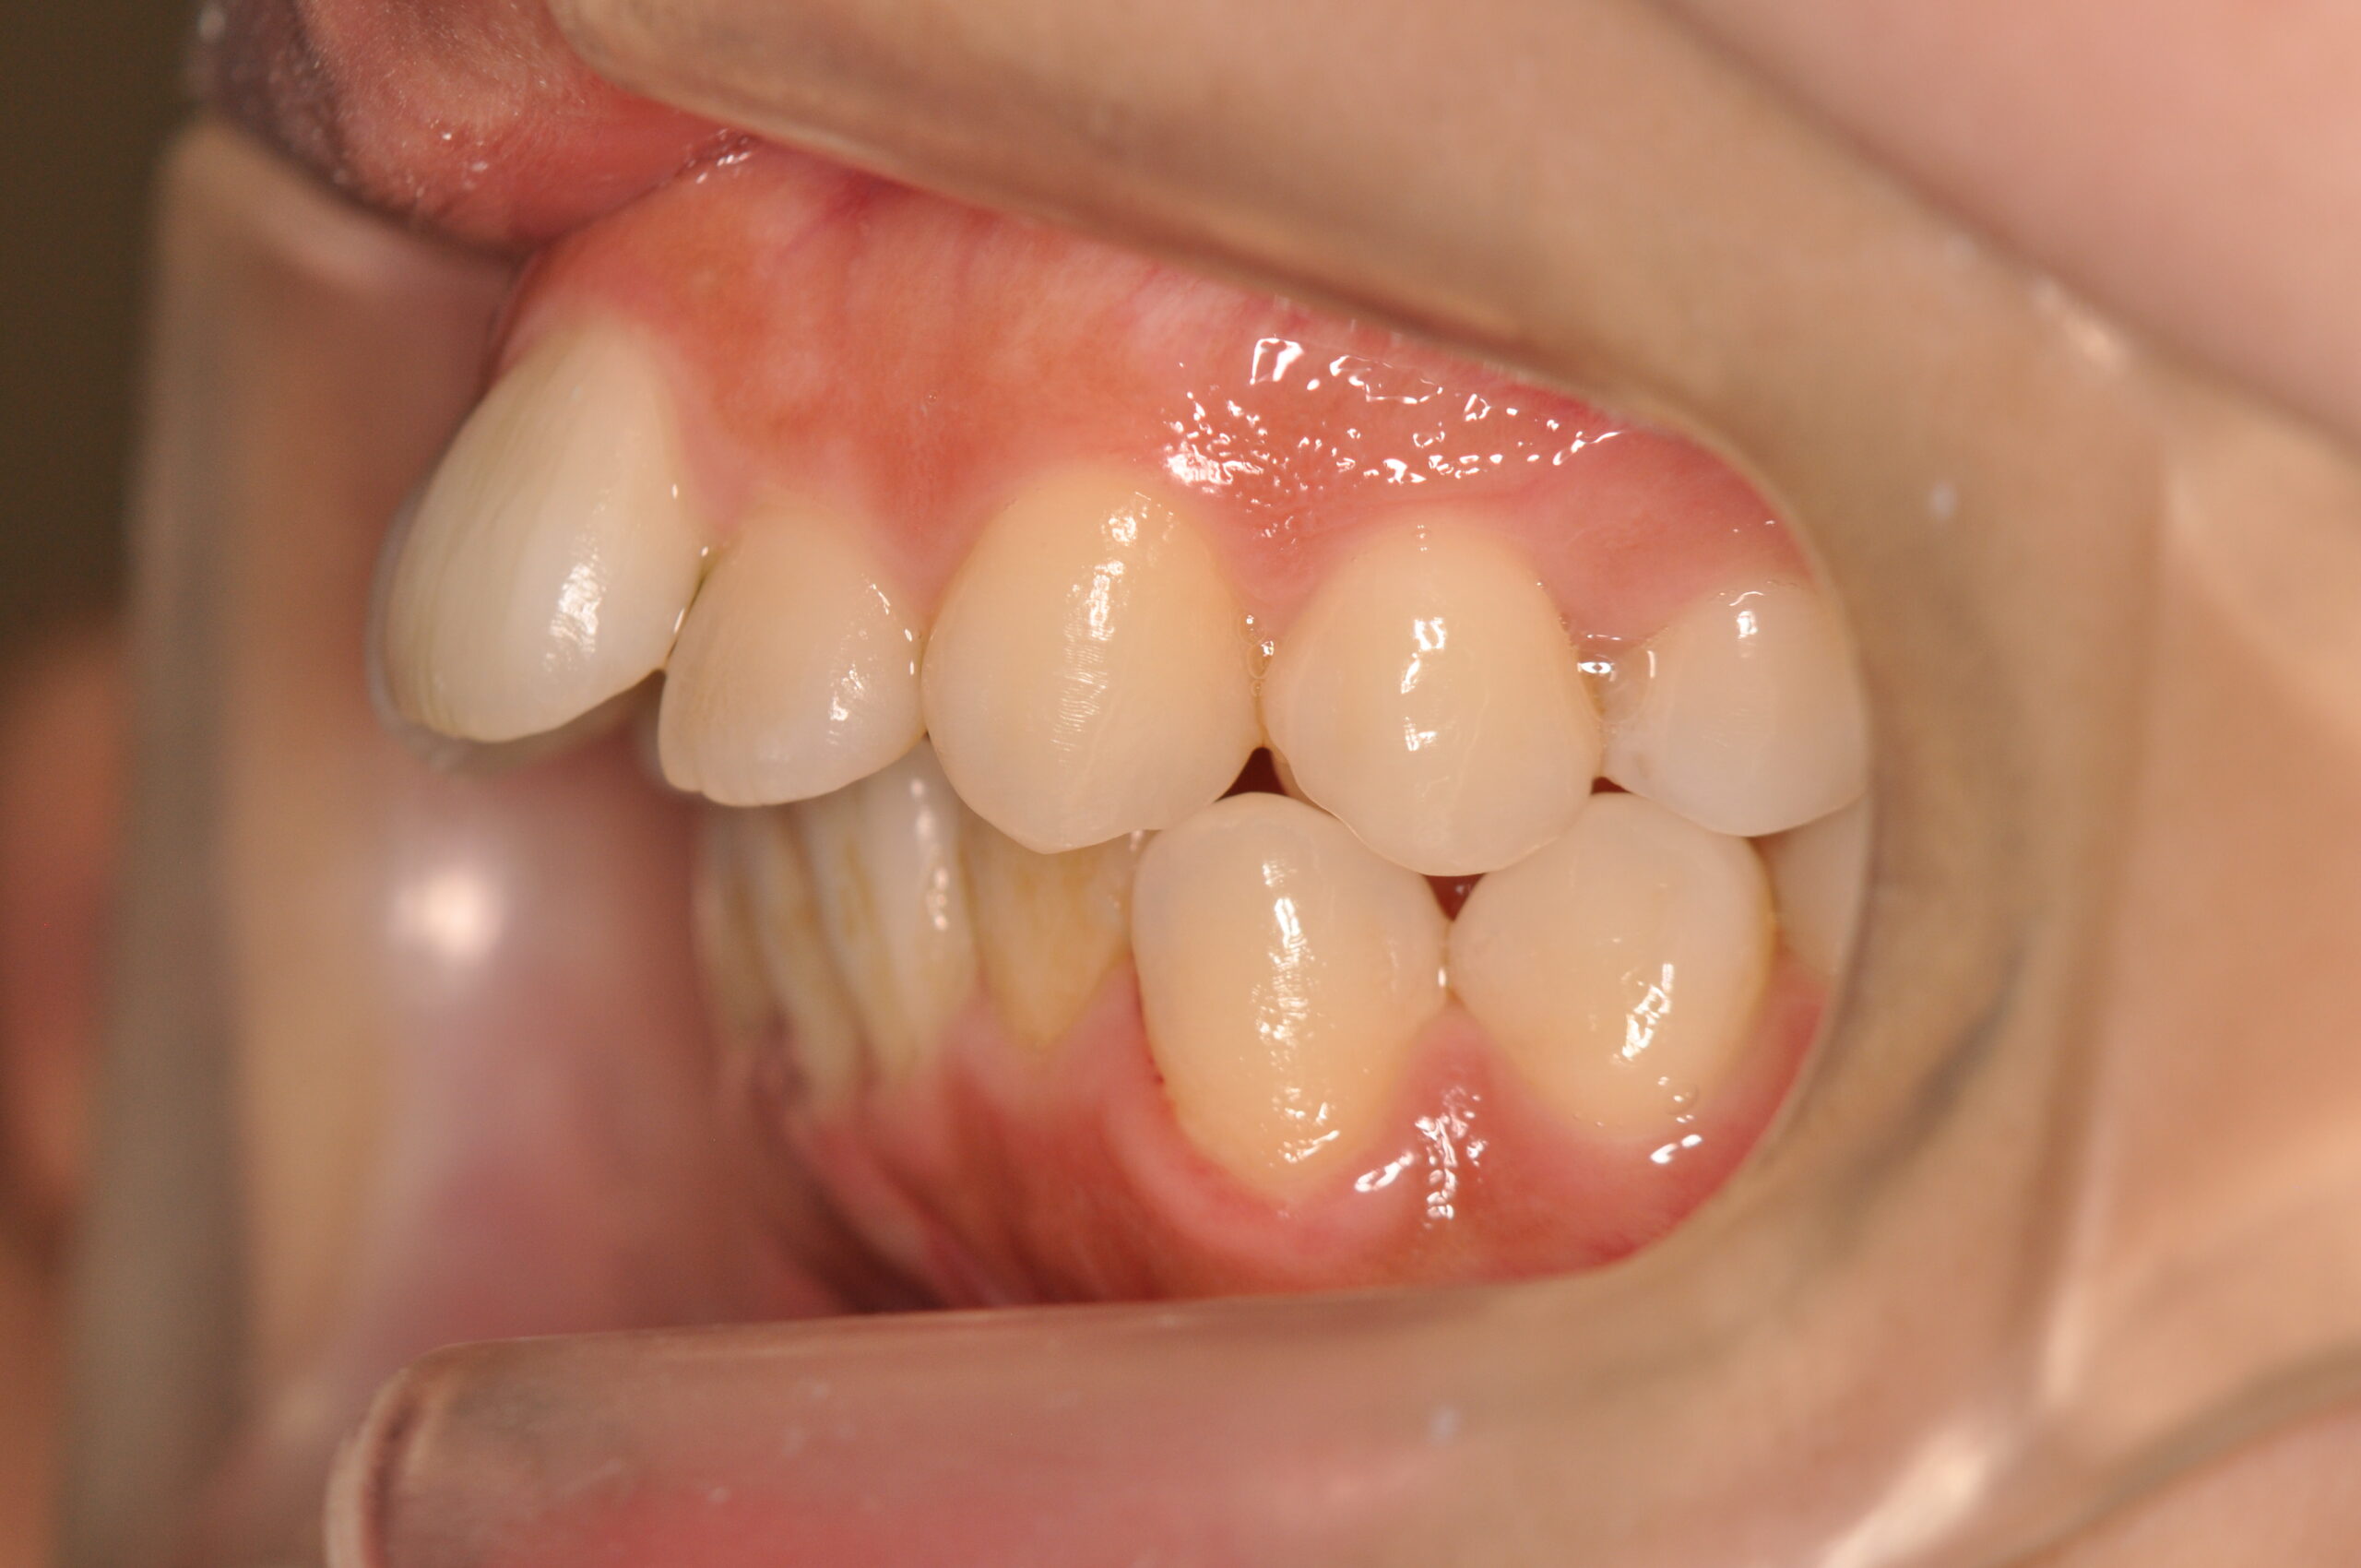

上顎前突・叢生(抜歯)[2555]

初診時

年齢

20歳5ヶ月 性 別 女性

治療期間 2年11ヶ月 費 用 矯正施術料:1,000,000円 調整料:4,000円/月

治療内容の詳細 初診時20歳の女性で、前歯が出ていて常に口が開いてしまうことを気にされ来院されました。

検査の結果、上顎前突及び上下顎前歯部叢生を伴うアングルⅡ級1類不正咬合と診断しました。

治療としては、上顎左右第1小臼歯を抜歯し、セルフライゲーションブラケット装置(デーモンシステム)で歯の配列を行いました。

同時に顎間ゴムにて咬合関係の改善を行いました。

この際、上顎に歯科矯正用アンカースクリューを設置し上顎前歯部後退時の土台としました。

治療期間は、2年11ヶ月でした。